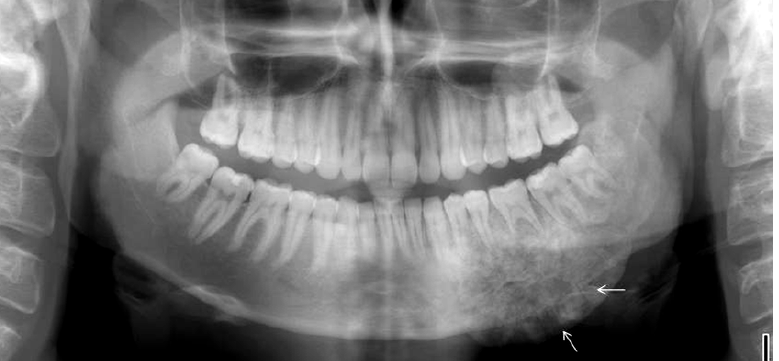

condensing osteitis

features of condensing osteitis

non-vital tooth or presence a source of inflammation

widened PDL

sclerosis of bone around roots in response to chronic inflammation

may mimic idiopathic osteoscerosis